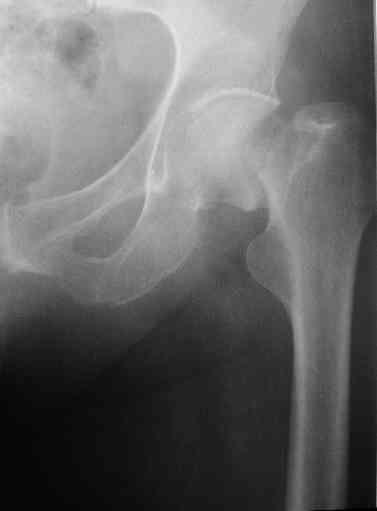

Перелом бедра, через неделю после эндопротезирования.

Уважаемые участники форума, просьба высказать Ваши мнения по представленному случаю. На прошлой неделе пациентке 74 лет, было выполнено цементное эндопротезирование тазобедренного сустава по поводу перелома шейки бедра.

Активизирована на следующий день, ходила с костылями, нагрузка полная. Дело близилось к выписке, когда она, поскользнувшись, упала в палате и получила то, что видите на снимках.Что бы Вы стали делать в подобной ситуации? Заранее спасибо.

A female 74 y.o. fell at day 7th after cemented THA. The femur is split from the tip of the troch (preexisted crack?) and fracture goes below the tip of the stem. Images attached. What type the fracture is according to Vancouver classification? We consider some kind of plating. What type of implant would you prefer? How long the plate should be? Is cable technique necessary? Grafting? Any probable pitfalls to concern? THX!